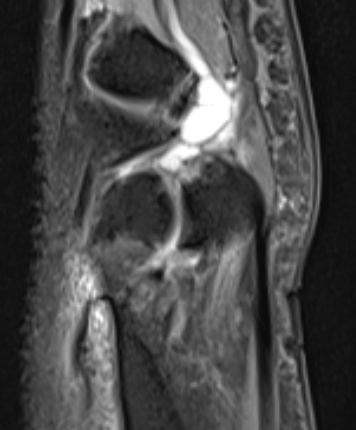

Dorsal ganglion

Dorsal ganglion arising from scapholunate joint

Dorsal ganglion arising from scapho-lunate joint